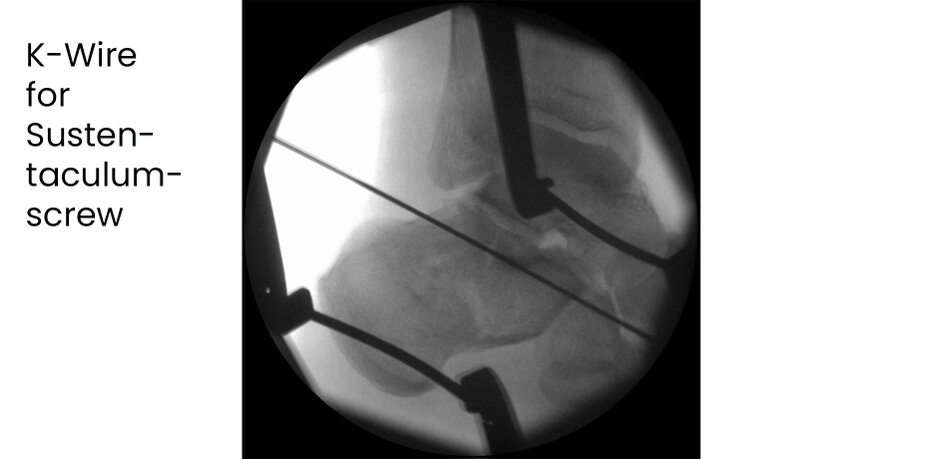

Case 17KL, male, 35y, surgery on day of trauma